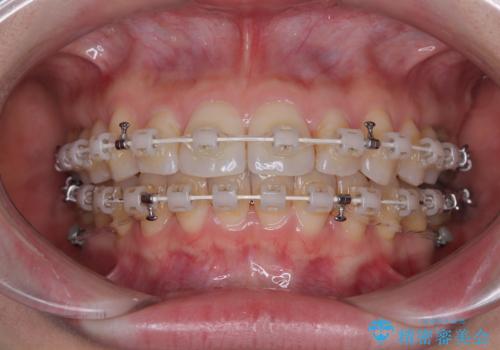

上下前歯のデコボコ ワイヤー装置で楽ちん矯正治療

- 前歯のデコボコや、やや突出した感じを気にして来院された患者様です。

抜歯矯正を必要とするほど口元の突出感はなく、本人もそこまでは気にしていない様子でした。

お仕事柄、マウスピース装着は困難とのことで、表側のワイヤー矯正にて治療を行うこととしました。

デコボコ解消の際に、前歯が前突するリスクがあったため、舌突出癖の改善と、アンカースクリューによる加強固定を行うこととしました。